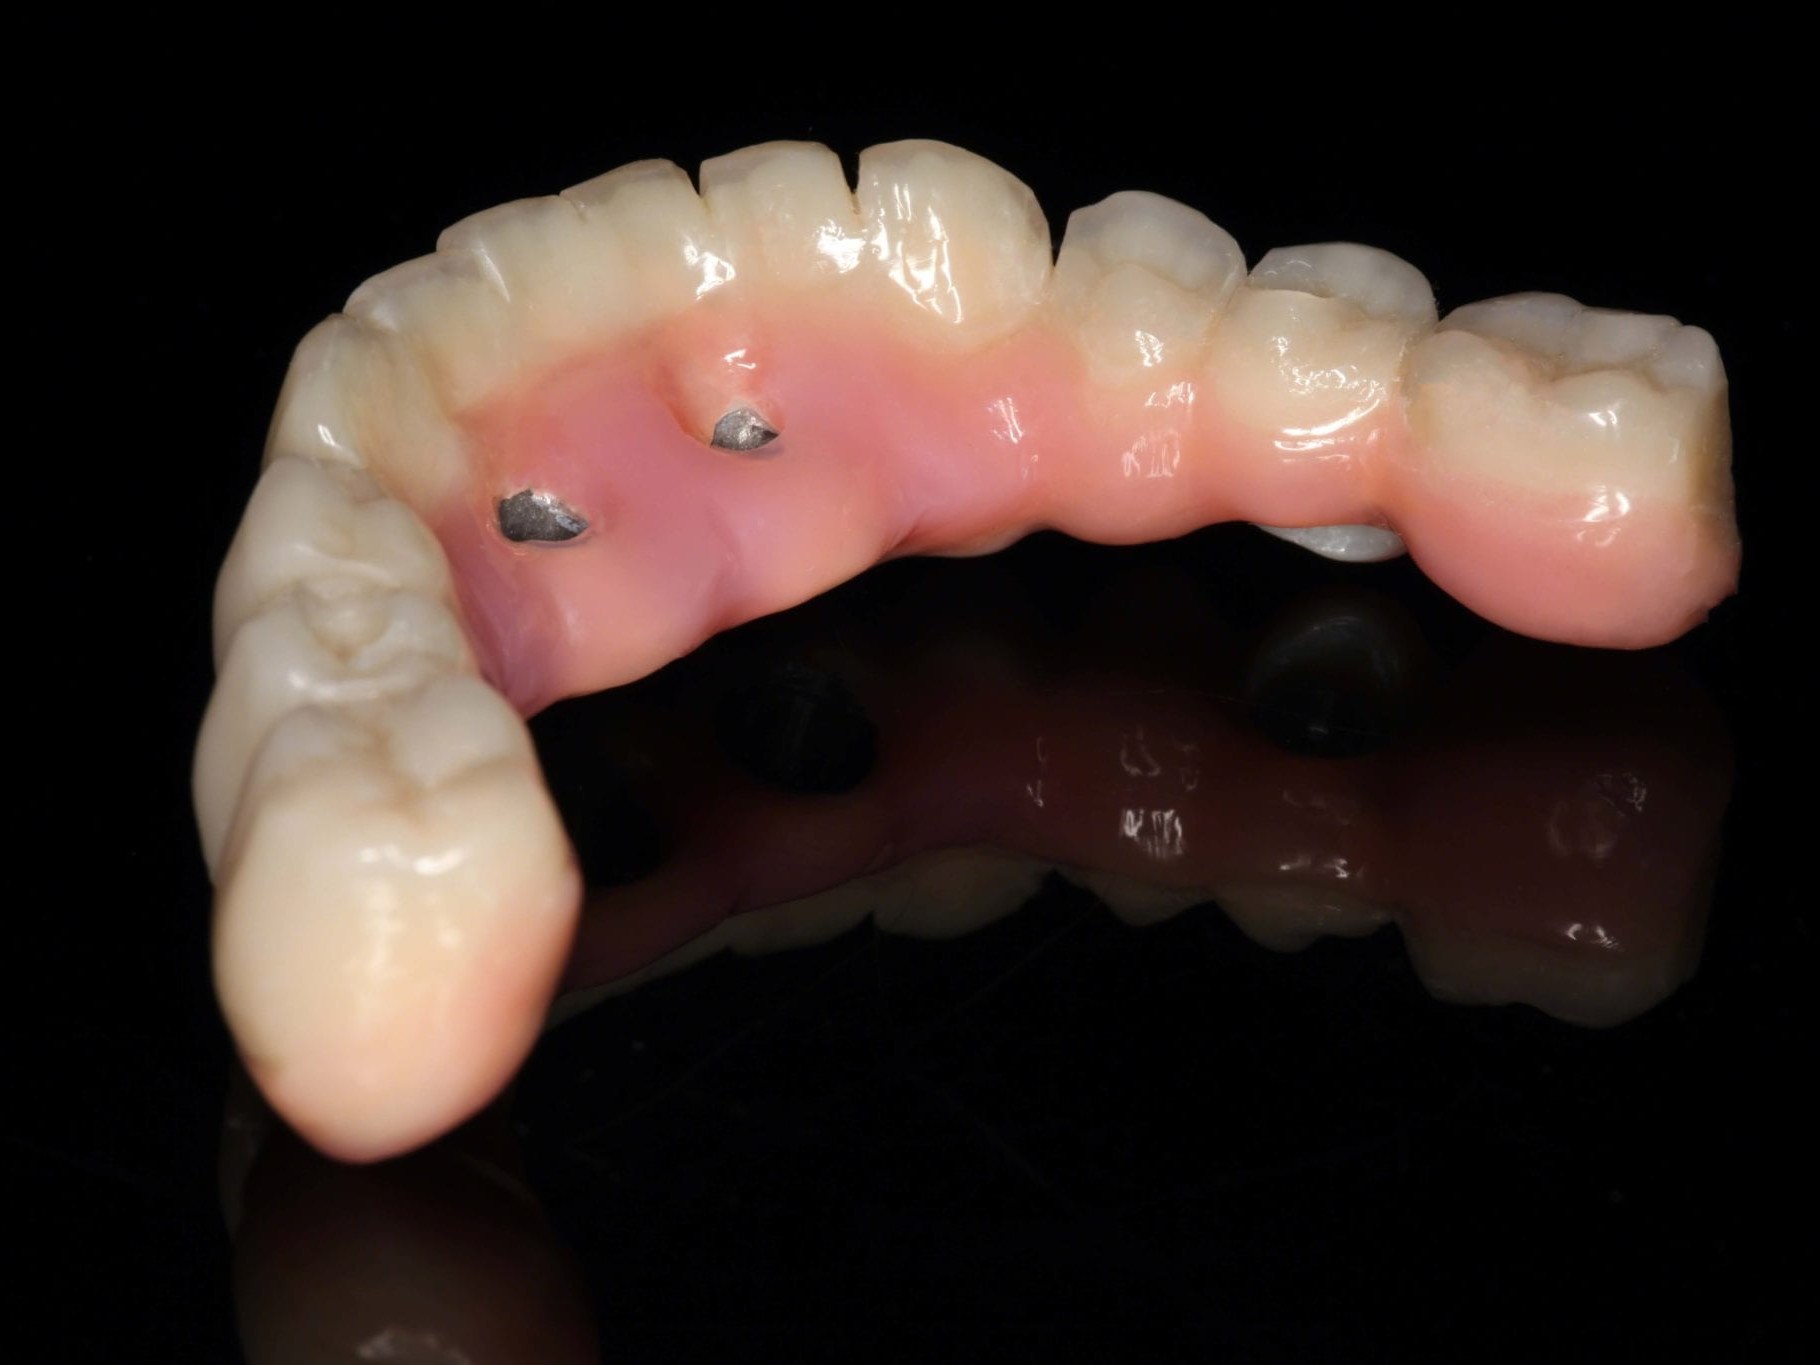

Wie weiter oben bereits beschrieben ist die Patientin im Oberkiefer mit einer keramisch verblendeten implantatgetragenen Brücke versorgt. Aus Sicht des Behandlungsteams schied daher eine keramische Verblendung des Unterkiefers aus. Die Verwendung von einem Composite mit keramischer Füllstruktur gewährleistet neben der notwendigen Farbstabilität und Plaqueresistenz zwei weitere Vorteile. Auf der einen Seite entsteht im Okklusionsmoment nicht das „keramische Klacken“ und zum anderen werden die auftretenden Kaukräfte gleichmäßiger auf das Implantat und den Knochen verteilt . Gerade bei implantologischen Oberkiefer- und Unterkieferversorgungen ist dieser „Stoßdämpfer–Effekt“ für den Langzeiterfolg wichtig. In dem vorliegenden Fall wurde die okklusal verschraubte Brücke aus einem massiven Titanblock gefräst (Abb. 4 und 5), wodurch das Endprodukt frei von aus der Gusstechnik bekannten Lunkern oder Verzügen ist. In Übereinstimmung mit den als Sheffield-Test ⁷ bekannten Kriterien der University of Sheffield, GB. ermöglicht dieser Fertigungsprozess gepaart mit der verblockten Abdrucknahme einen präzisen und somit spannungsfreien Sitz der Brücke – sowohl auf dem Meistermodell als auch im Munde des Patienten. Sowohl die Verblendungen der Zähne als auch des Zahnfleisches wurden unter Zuhilfenahme der diagnostischen Aufstellung mit visio.lign ⁸ im Labor angefertigt. Hierbei wurde besonderer Wert auf die naturgetreue Nachbildung der Rot-Weiß-Ästhetik und eine gute Hygienefähigkeit gelegt. Die Vorteile dieses Verblendsystems liegen in der exakten Umsetzung von der Aufstellung hin zur fertigen Arbeit durch mehrschichtige Verblendschalen (Abb. 6). Diese Verblendschalen werden schon bei der diagnostischen Aufstellung individualisiert und nach der Gerüstfertigstellung weiterverarbeitet. Mit passenden Individualisierungs- und Ergänzungsmassen sowie einem farblich abgestimmten Verbundsystem mit sehr guter Druck-Scheer-Festigkeit ⁹ ermöglicht dieses System durch Hinterlegen mit Intensivfarben das Gestalten von Mamelons ebenso wie die individuelle Gestaltung von Dentinleisten. (Abb. 7 und 8). Nach der zahntechnischen Erstellung der Unterkieferbrücke wurde diese intraoral inkorporiert (Abb. 9a). Die Implantatschrauben wurden mit 25 Ncm angezogen. Ein wichtiger Hinweis ist, dass hier stets das Originalequipment des Herstellers oder ein elektronisch kalibrierter Schraubendreher seine Anwendung finden sollte. Die Schraubenkamine wurden initial mit einem bakteriendichten, formstabilen lichthärtenden temporären Füllungsmaterial ¹⁰ verschlossen (Abb. 9b). Nach 6 Wochen werden die Implantatschrauben seitens des Prothetikers nochmals kontrolliert und ein abschließendes OPG erstellt (Abb. 10).